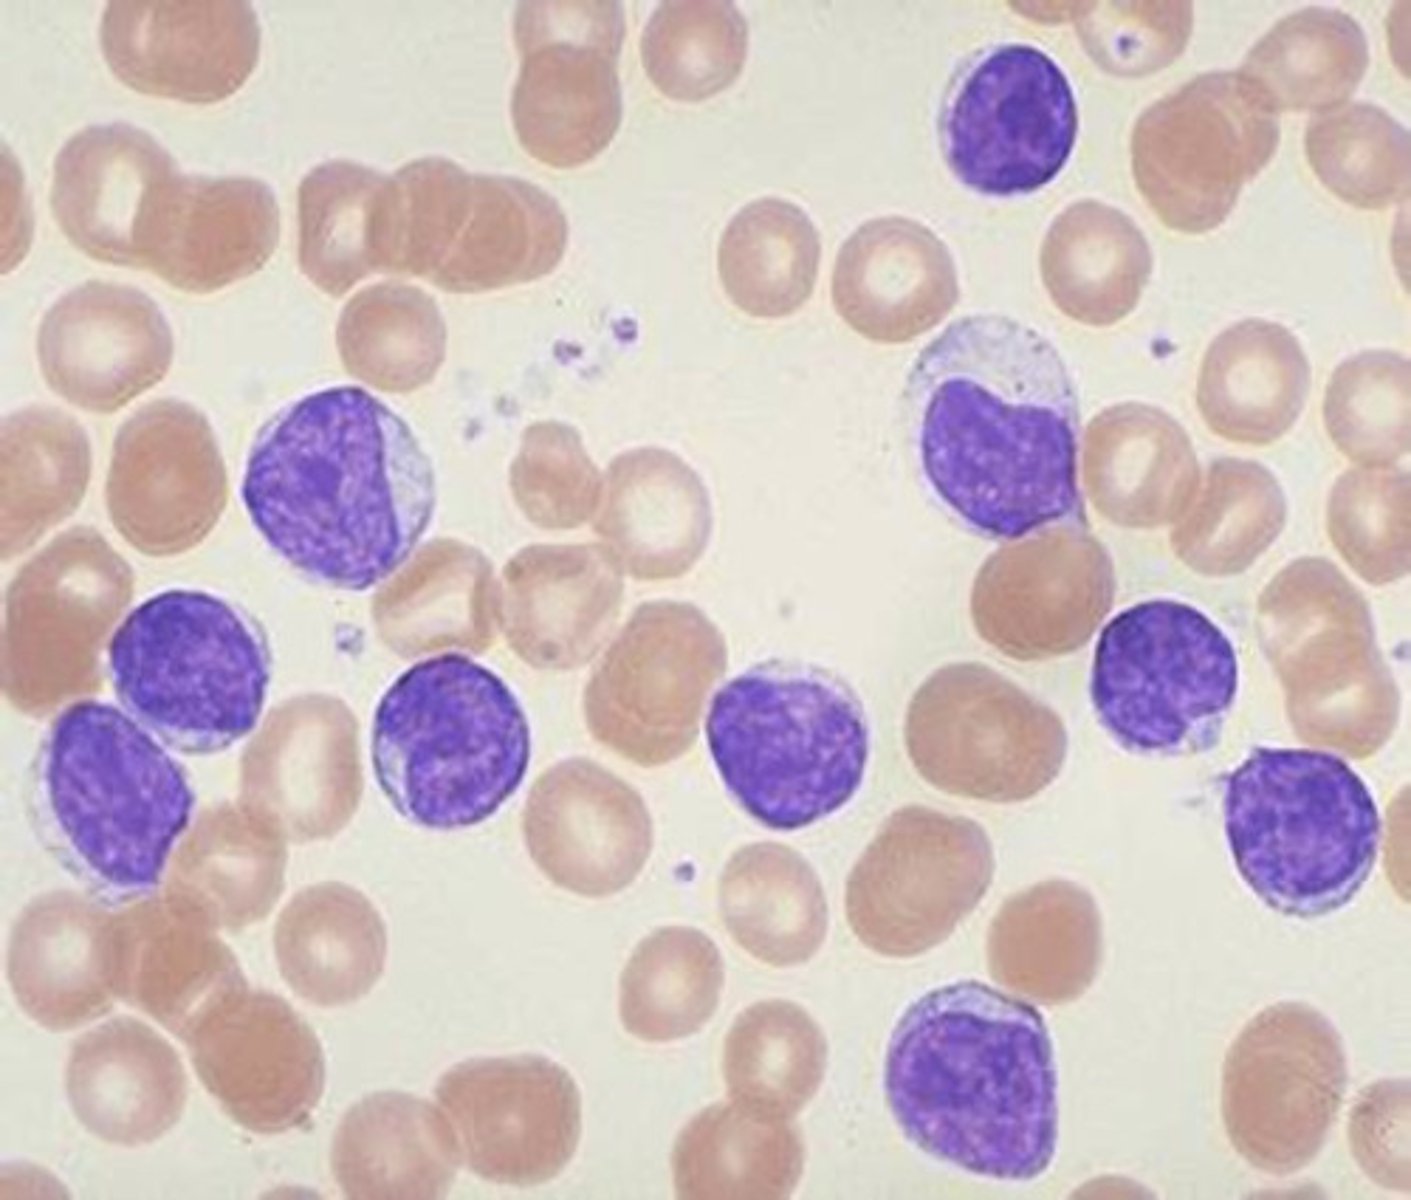

Infectious mononucleosis

Definition: Kissing disease

Etiology: Epstein-Barr virus (EBV)

S+S: Sore throat, fatigue, fever, enlarged spleen, large number of BIG lymphocytes

Treatment: Rest + no exercise

Pathogenesis of mono

EBV enters and multiplies in epithelial cells in mouth --> Spreads to B cells in the throat --> Infected B cells multiply --> Signs and symptoms --> Cytotoxic T cells and NK cells destroy infected B cells --> Recovery